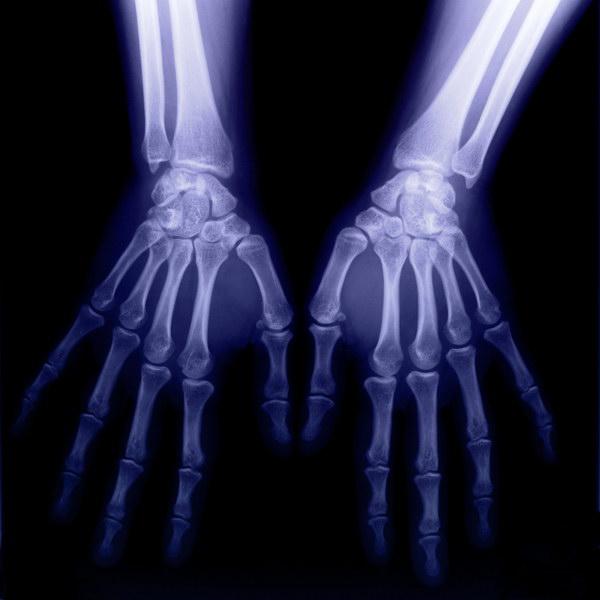

01、X线--X-ray

▲ X线像被压扁的香蕉

X光检查,也叫拍片子,其实和拍照片差不多。它有很强的穿透能力,检查时就像给身体拍了一张平面影像的照片。

由于被照射物体密度的不均匀,拍摄的底片上会形成黑白不一的颜色.所以它一般只能发现较明显的病变组织和结构,由于价格便宜,辐射量小,一般是疾病初筛的首选。但是X线会使生物细胞受到破坏,一般情况下,孕妇、备孕人群不建议做X光,以免影响胎儿。

X线常用于肺部及骨骼系统疾病的检查,尤其对于检查急诊骨折、骨肿瘤有着不可替代的作用,只有遇到局部结构显示不清或要观察病灶周边侵犯的情况时,才需要进一步做CT检查。

4、骨骼及四肢最常用的检查是X光,如诊断不明,需进一步观察,可用CT。除此之外,关节软组织、骨肿瘤的检查可用核磁共振。